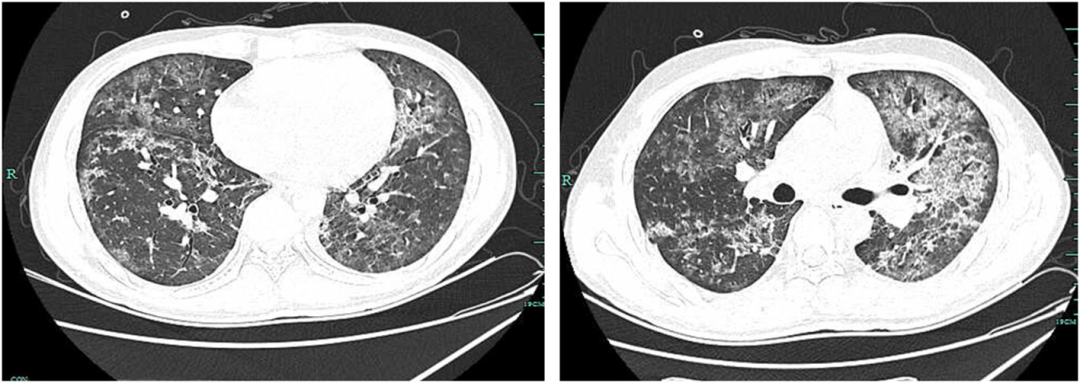

• 根据mNGS结果,针对性给予美罗培南1g q8h和卡泊芬净70mg,甲基强的松龙40 mg BID

• 第12天,患者临床症状有所缓解,肺部CT较之前明显改善(图5)

图5:第12天,肺部CT示双肺多发感染,较前好转,略弥漫,伴磨玻璃样高密度影